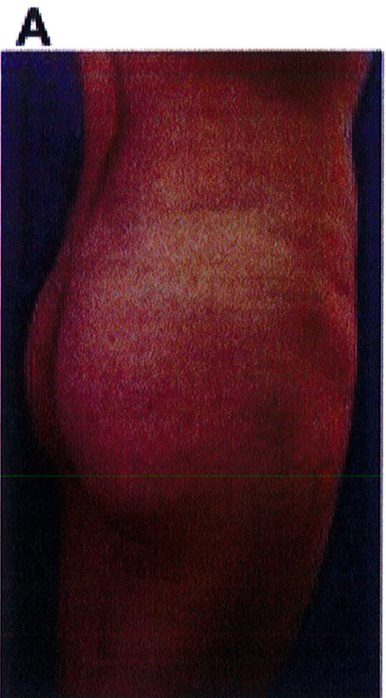

Hình. 19. . (A) Hình anh trước và (B) và sau phẫu thuật làm đầy mông của bệnh nhân chùng da vùng mông tương đối nhiều. Bệnh nhân được đặt khối implant dưới cân thể tích 330 mL ở hai bên.

Bệnh nhân 52 tuổi xuất hiện chùng da vùng mông (mức độ nặng), mong muốn giải quyết vấn đề này đồng thời tăng kích thước vòng ba. Hai khối anatomic implant

thể tích 330mL dạng silicone được đặt ở dưới cân cơ mông lớn.Hậu phẫu đánh giá thấy giảm thời gian hồi phục (Hình 19).